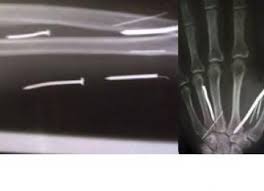

Pasangan itu menyiksa PRT tersebut dengan memalu 24 paku di tangan, kaki dan dahi wanita itu, kata mereka.

Ariyawathi dibawa ke rumah sakit untuk menjalani operasi pengeluaran paku dari tubuhnya, yang kata pembantu itu ditancapkan ke tubuhnya ketika benda-benda itu dalam keadaan panas.

Pemeriksaan dengan sinar X menunjukkan bahwa paku-paku dengan panjang satu hingga dua inci berada di tangan dan kakinya, dan satu paku di dahinya, kata beberapa pejabat.